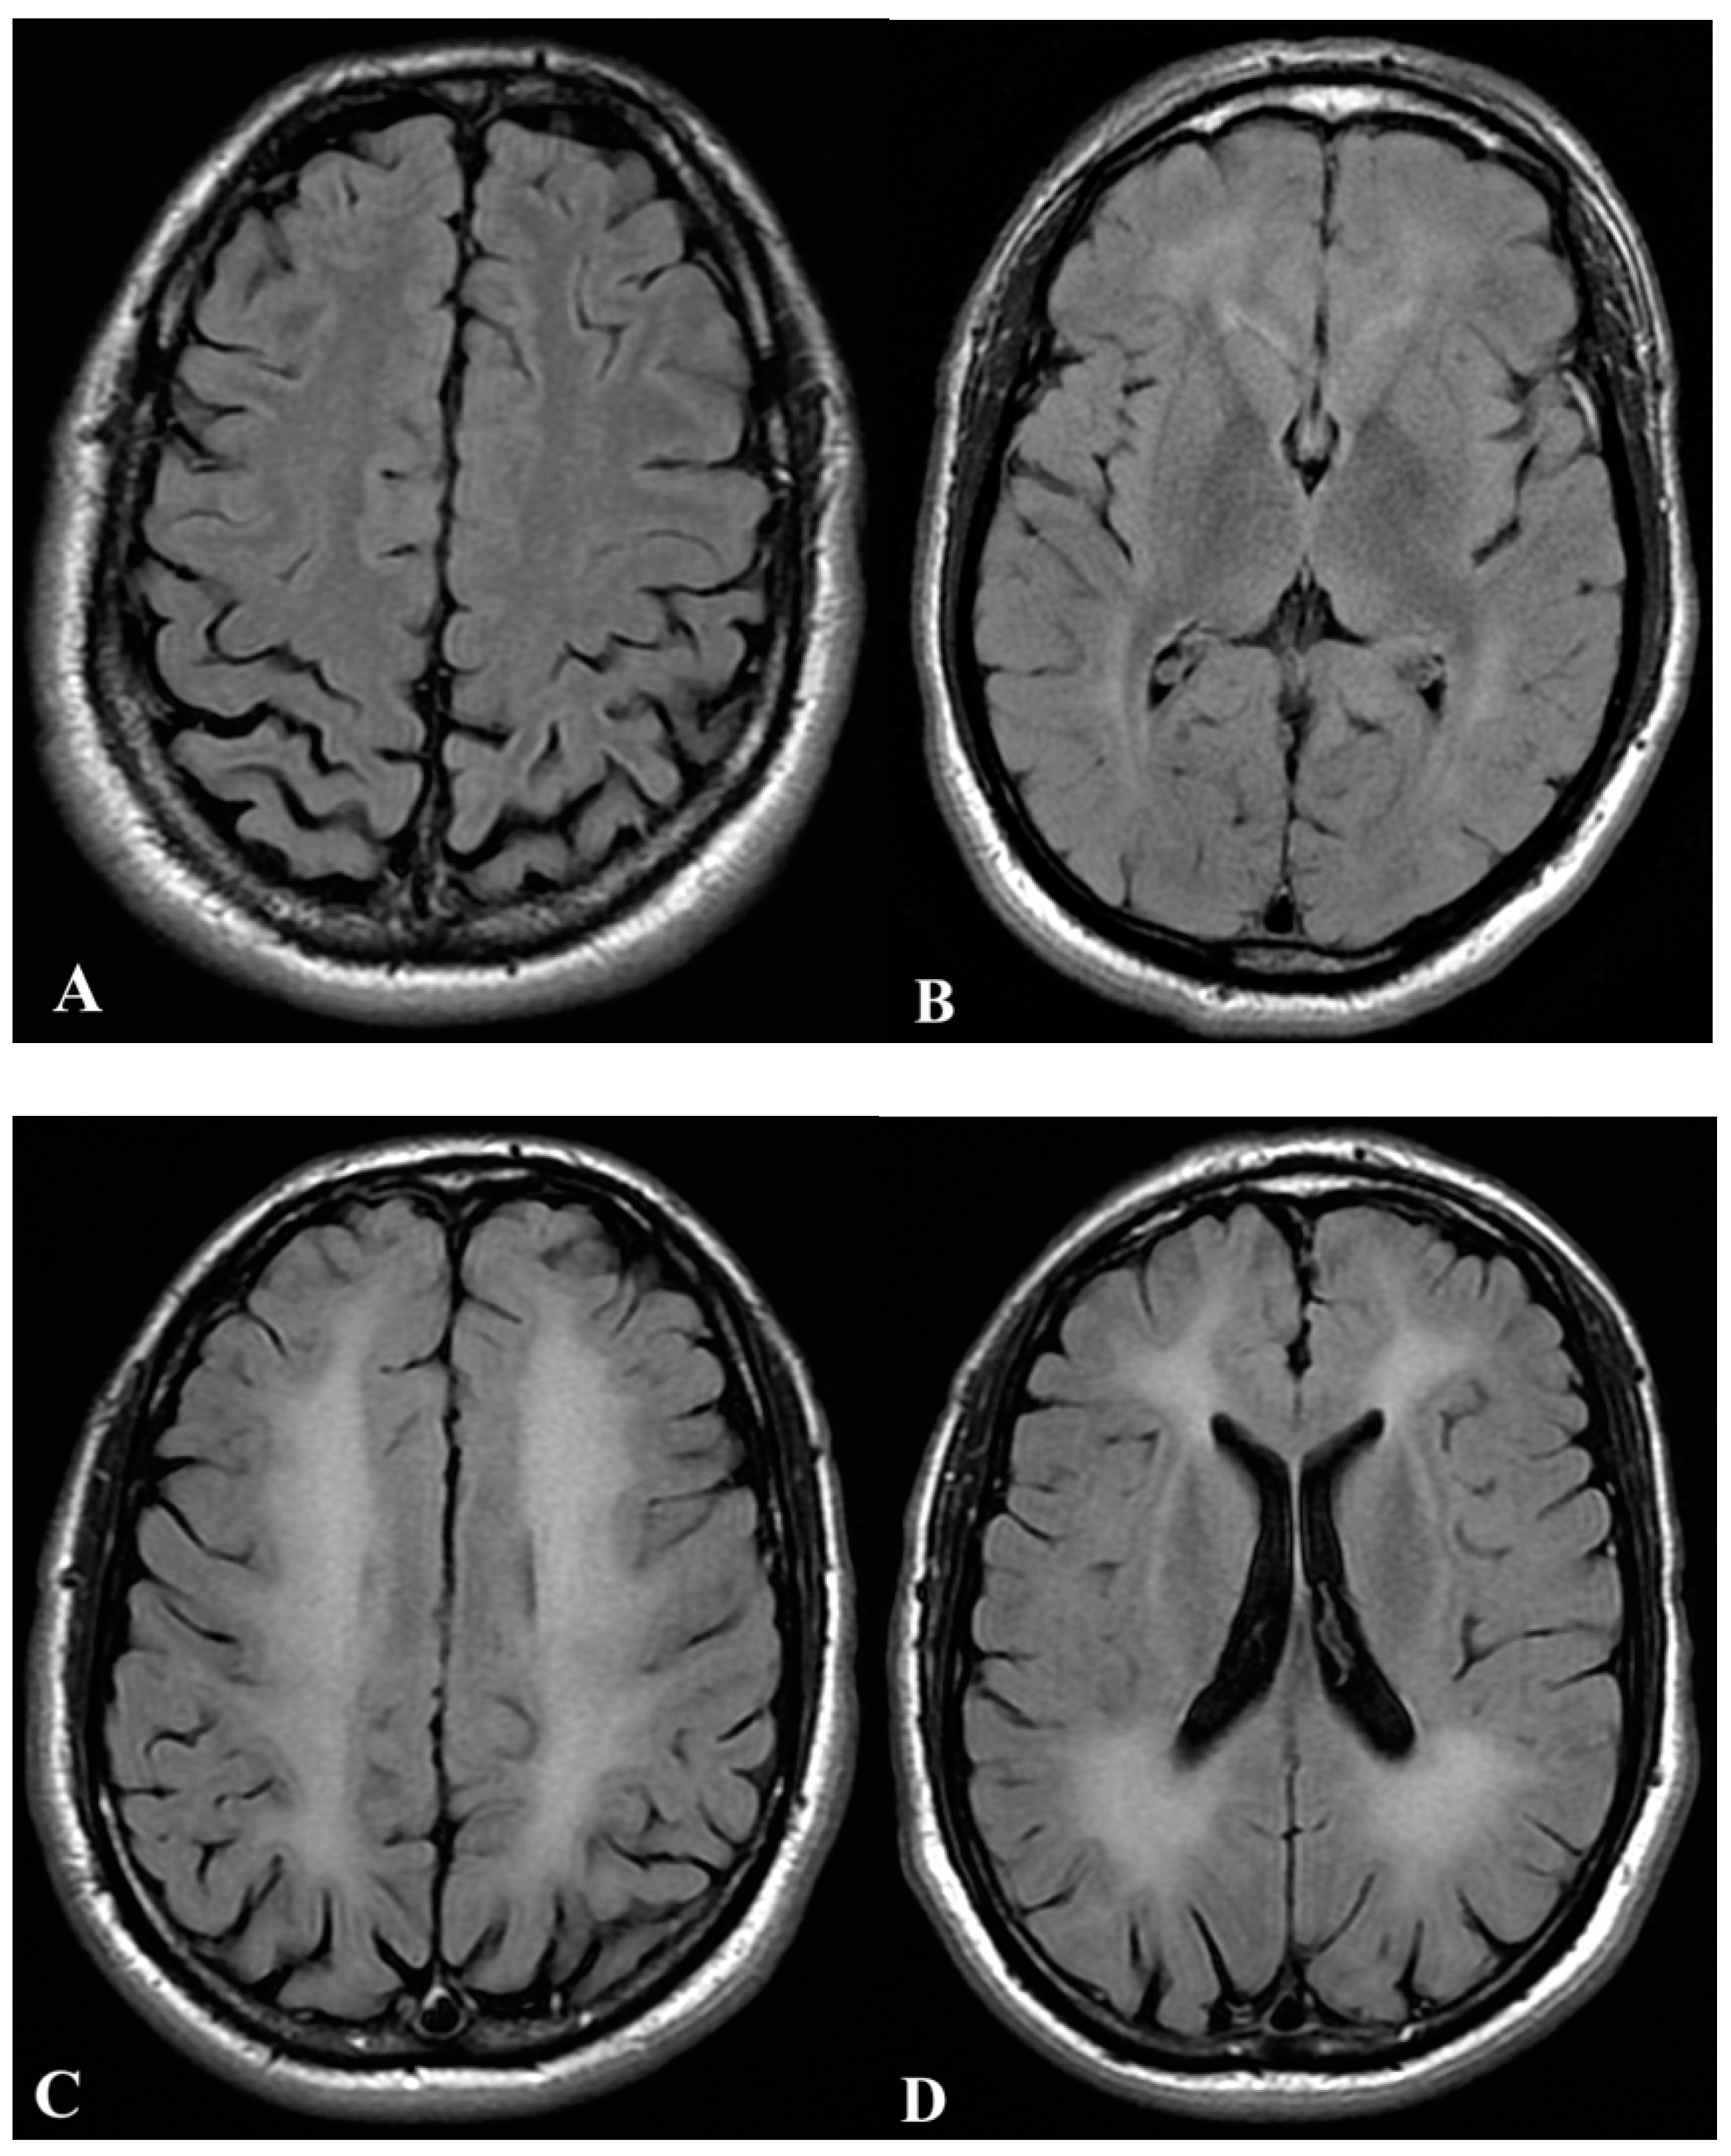

2.1. First Case

2.2. Second Case